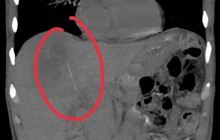

Dị vật là cây bút được bác sĩ lấy ra khỏi bàng quang của bệnh nhân

Tại bệnh viện, việc thăm khám ban đầu gặp nhiều khó khăn do bệnh nhân mới ở tuổi dậy thì, không thể tiến hành kiểm tra xâm lấn. Ê-kíp điều trị đã chỉ định siêu âm và phát hiện dị vật là một cây bút nằm trong bàng quang.